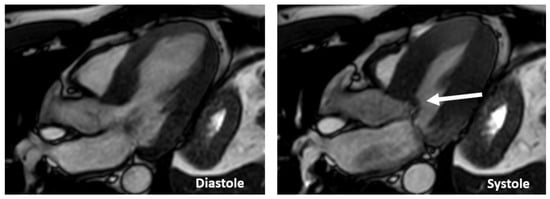

Cardiac magnetic resonance (CMR) protocols in HCM should always include an assessment of the mitral valve, with slices positioned perpendicular to the valve plane (through-plane) along with in-plane views of the valve orifice. Velocity-encoded CMR imaging is added to determine the peak velocity of blood flow through the left ventricle [21].

CMR is superior to standard 2D echocardiography in the detection of LV apical and anterolateral hypertrophy, apical aneurysms, thrombi, myocardial crypts, and papillary muscle abnormalities; however, small structures, such as the mitral valve apparatus, are not well-visualized because imaging slices in CMR are thick and potentially lead to partial volume artifacts (Figure 11).

Accurate quantification of LVOTO is time-consuming, prone to error and can only be measured at rest. For these reasons, Doppler echocardiography is the modality of choice for the quantification of LVOTO. In addition, CMR with gadolinium, via the distribution analysis of late enhancement, helps in the differential diagnosis of HCM with HCM phenocopies such as those of amyloidosis and Fabry disease (Figure 12).

Figure 11. Images of long-axis CMR view of a patients with HCM showing SAM (arrow).